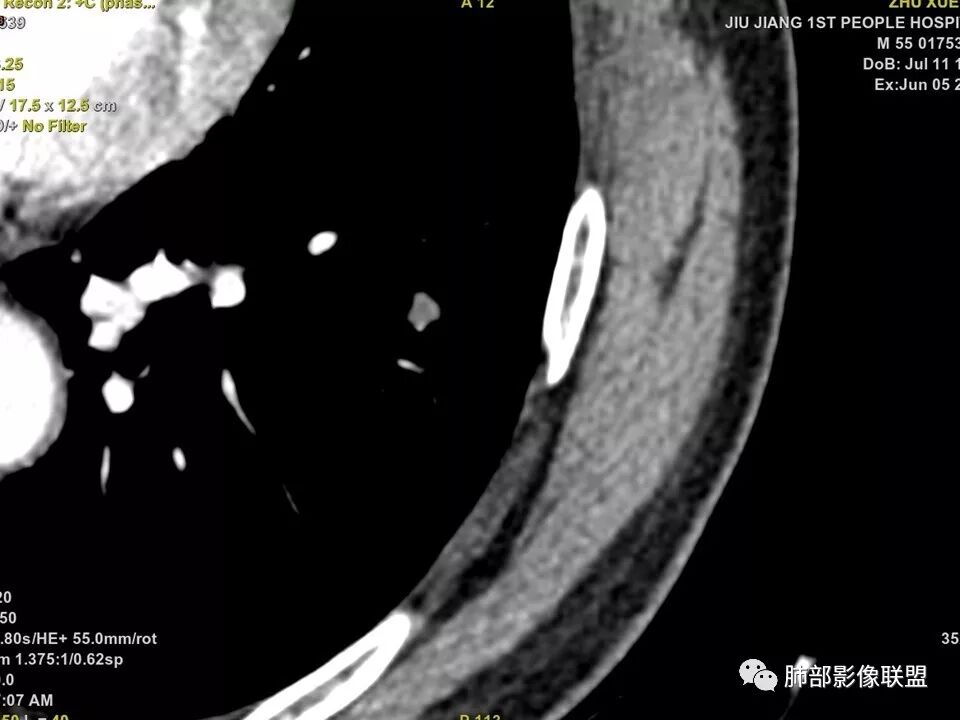

边缘有光滑,有圈黑晕,强化弱,似乎有脂肪密度,支气管截断的部位很自然,没有鼠尾状狭窄,考虑软骨型错构瘤?

这个支气管开口位置,如果是肿瘤应该有管壁浸润,也应该有膨胀感,这个没有,不像恶性肿瘤的支气管截断

病灶部分平直丶内收,有脂肪密度,不强化支持错构瘤。部分病灶有结节堆积感,分叶,与支气管、肺动脉关系密切,需鉴别腺癌。不强化进一步结核结节。

左肺下叶前基底段结节,病灶边缘分叶,边缘平直,u型征,可见气管截断,增强可见病灶边缘血管,平扫ct值低,轻度强化。考虑良性病变。

晨读病例,强化值小于20,还是提示良性,感觉支气管截断是坑,所以考虑错构瘤?肺癌待排

边缘平直,主要强化值小于20,说明基本不强化,提示良性

典型CT特征包括:(1)圆形或椭圆形边界清楚的病灶。(2)大小1~4cm,有轻微分叶改变。(3)较均匀的软组织影,多伴有钙化。(4)无毛刺,卫星灶及肺门或纵隔淋巴结肿大。(5)CT增强扫描无强化或轻度强化,其强化可能与软骨瘤间质中的薄壁血管或周围慢性炎症反应有关。

鉴别诊断,主要是错构瘤。错构瘤是肺内最常见的良性肿瘤。错构瘤内常见“爆米花”样钙化,而软骨瘤钙化则多呈点状或环状钙化。病灶内脂肪密度影是错构瘤的特异性征象,而软骨瘤内无脂肪成分。此外尚需要与肉芽肿性炎、硬化性肺细胞瘤、肺癌、转移等鉴别。